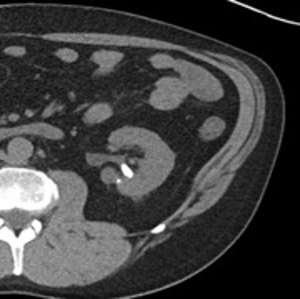

74-year-old male with a past medical history of nephrolithiasis, sleep apnea, thoracic aortic aneurysm, activated protein C resistance, Factor V deficiency, Gout, Hypertension and benign prostatic hyperplasia (BPH) presented for further evaluation regarding nephrolithiasis. The patient recently underwent extracorporeal shock wave lithotripsy (EWSL), and a post operative abdominal x-ray showed a calcification at the level of the right sacrum and a right ureteral stone could not be ruled out. A non-contrast CT abdomen and pelvis was ordered, which showed severe right hydroureteronephrosis due to two stacked distal right ureteral stones measuring 11 mm in size (Figure 3). Hounsfield units of the ureteral stones averaged 1895.

The patient underwent a right ureteroscopy and laser lithotripsy. Using a semi-rigid ureteroscope, a large impacted and obstructing stone was encountered. A hydrophilic wire was advanced past the stone into the renal pelvis. A ureteral catheter was advanced over the hydrophilic wire into the renal pelvis under fluoroscopic guidance, and the hydrophilic wire was exchanged for a super-stiff wire. Due to edema and tortuosity of the ureter, the semi rigid ureteroscope could not safely maintain visualization of the stone. Therefore, a 12/14 Fr x 28 cm ureteral access sheath was advanced to the level of the stone and a flexible ureteroscope was advanced to the level of the stone, to allow optimal visualization and laser lithotripsy.